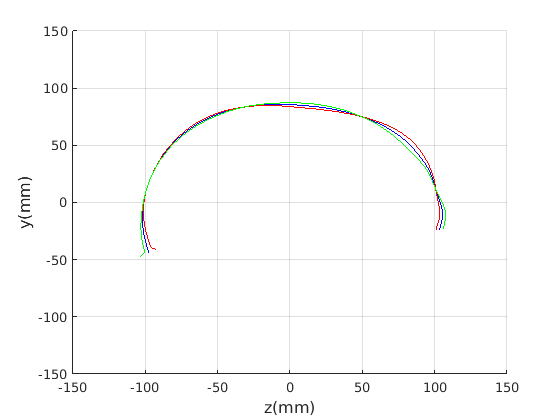

Figure 16 shows examples of the robust ellipse fit for four head profiles. The centre of the ellipse is used in a pose normalisation procedure where the ellipse centre is used as the origin of the profile and the angle from the ellipse centre to the nasion is fixed at -10 degrees. We call this Ellipse Centre - Nasion (ECN) pose normalisation and later compare this to GPA. The major and minor axes of the extracted ellipses are plotted as red and green lines respectively in Fig. 16.

|

Figure 17 shows all 100 profiles overlaid with the same alignment scheme. The median value of major ellipse axis and the ellipse centre-nasion angle differ by 3.6 degrees, so that when the nasion angle is fixed at -10 degrees, the median ellipse angle is -6.4 degrees (cf. -7.4 degrees with manual landmarking of the nasion). We noted regularity in the orientation of the fitted ellipse as is indicated by the clustering of the major (red) and minor (green) axes in Fig. 17 and the histogram of ellipse orientations in Fig. 18. For most people, the major axis of the ellipse is closely aligned with the y-axis (upright), and titled slightly forwards. A minority of heads (9%) in the training sample have their major ellipse axes closer to the vertical (these relatively tall and short heads are known as brachycephalic.) Ellipse axis clustering (relative to the fixed ellipse centre-nasion line) does not appear to be sharply defined. This is because many crania are close to circular in cross-section, making the orientation of these angles sensitive to small changes in shape from one person to the next. Note also the variation at the back of the head due to a variety of hair styles, some of which protrude from under the cap. We limit the region over which we model the cranial shape in order to crop this unwanted data out.